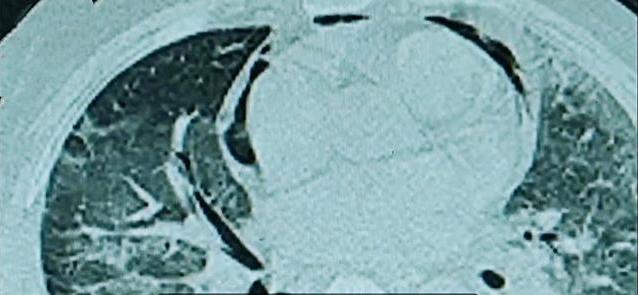

空调久未清洗“军团菌”有可能被吸进肺-新华网

近期,多地媒体报道了使用未清洗空调后,肺部感染“嗜肺军团菌”的病例。记者走访厦门医学院附属第二医院、厦门市中医院、厦门医学院附属海沧医院等多家医院后获悉,厦门...

空调长期不洗男子吹空调后肺部感染险丧命

近日,福建福州一男子在家开启半年未清洗的空调,连吹两天后开始咳嗽不止。咳嗽两天后一度神志不清,出现呼吸衰竭被送进医院ICU。该男子被确诊感染了“嗜肺军团菌”,...

空调长期不洗男子肺部感染险丧命长期不洗的空调有什么病菌?

福建福州一男子在家开启半年未清洗的空调,连吹两天后开始咳嗽不止。咳嗽两天后一度神志不清,出现呼吸衰竭被送进医院ICU。该男子被确诊感染了“嗜肺军团菌”,出现大...